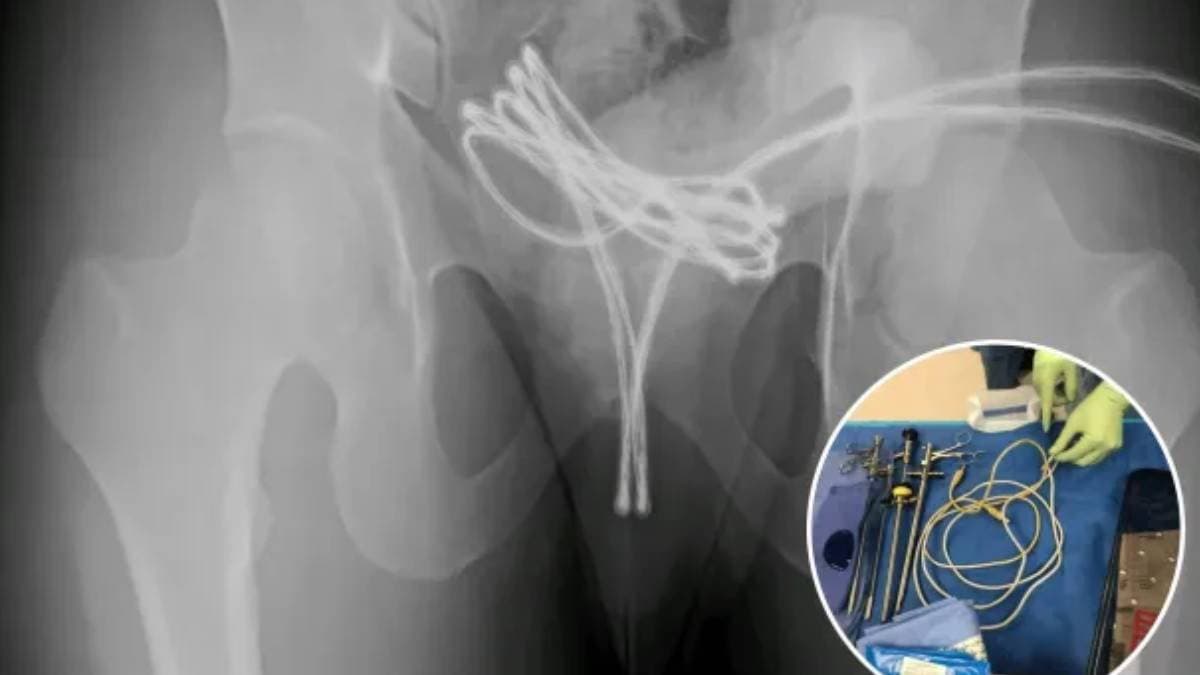

যৌন চর্চার নতুন ট্রেন্ড 'সাউন্ডিং', গোপনাঙ্গে 'তার' ঢুকিয়ে ত্রাহি ত্রাহি রব ছাত্রের, থ মেরে গেলেন চিকিৎসকরা!